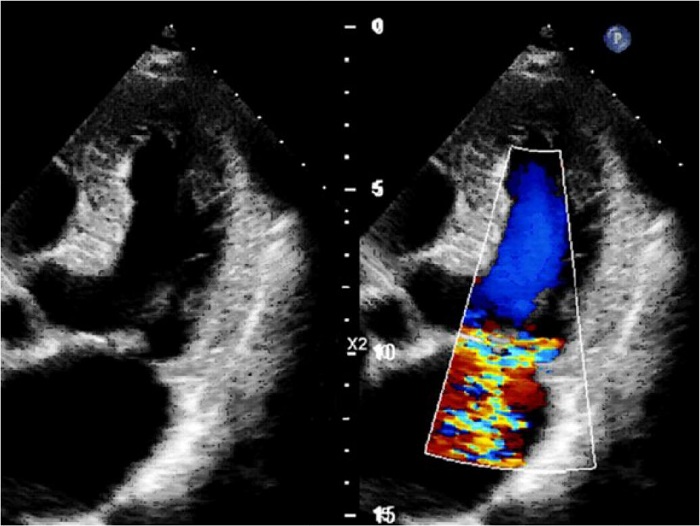

Transthoracic echocardiography (Figure 2) showed the mirror-imaged arrangement of the studied organs in comparison with the typical ultrasound image, i.e., the left-developed right-sided heart. A slight left atrial enlargement was detected (52*57 mm in the four-chamber view) without chamber hypertrophy, with normal left ventricular contractility (left ventricular ejection fraction in B-mode was 66%). A slightly dilated mitral annulus (36 mm) was detected; the ruptured chord of the posterior mitral leaflet in P3 segment and grade 2 mitral regurgitation were visualized. The effective regurgitant orifice was 21 mm. Other valves were functioning normally. The pericardium was not changed. The performed carotid Doppler sonography showed that the carotid artery wall was thickened; heterogeneous plaques of up to 10% were detected in carotid bifurcation, and the internal carotid artery orifices were on both sides.